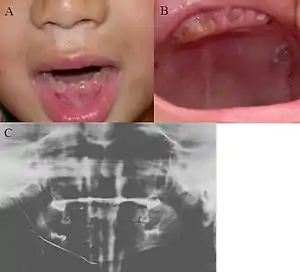

| Oral photographs from an individual with Dentinogenesis imperfecta | |

This condition can cause teeth to be discolored (most often a blue-gray or yellow-brown color) and translucent, giving teeth an opalescent sheen.[2][3][8][5][9] Teeth are also weaker than normal, making them prone to rapid wear, breakage, and loss.[2][3][4][5][8] These problems can affect baby (primary/deciduous) teeth alone, or both baby teeth and adult (permanent) teeth, with the baby teeth usually more severely affected.[5][8]

Clinical presentation

Clinical features include:

- Discoloured teeth - teeth may be amber, brown, blue or opalescent

- Bulbous shape to the tooth crown due to cervical constriction

- Tooth wear/Non-carious tooth surface loss (NCTSL) - due to the poorly mineralised dentine, the enamel of the tooth is unsupported and subsequently shears or chips off as it is subjected to biting forces. This exposes the underlying poorly mineralised dentine which is less resistant to wear. Therefore, features of abrasion and attrition may become apparent.

- Reduction in occlusal vertical dimension (OVD) - this is secondary to the tooth wear/NCTSL. A reduced OVD can lead to craniofacial dysgnathia, poor tooth aesthetics, and disorders during chewing, swallowing, speaking and eating.[2][3][4][5][8]

The baby (primary) teeth are usually more severely affected than adult (permanent) teeth.[3][5][8]

Radiographic presentation

Radiographic features include:

- Bulbous shape of tooth crown with pronounced cervical constriction

- Small pulp, or total pulp obliteration

- Small or obliterated root canal

- Presence of pulp stones

- Narrow and small roots

- Periapical radiolucency without any evidence of clinical pathology such as tooth decay (dental caries)[2][3][5][14]